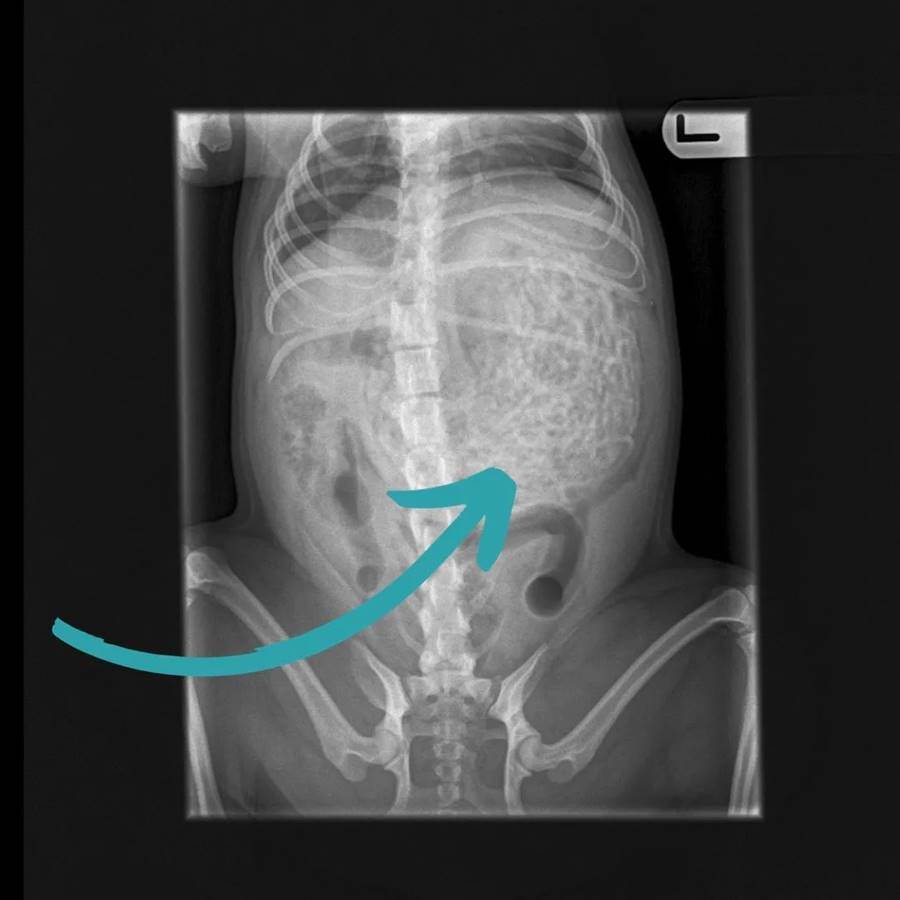

撿屎官擔心它出什麼問題,便帶去寵物醫院檢查,結果一看嚇一大跳,拍片子發現它腹部有很多奇怪的東西!

醫生緊急手術,進一步的檢查,最后竟取出50多條發帶皮筋,至少有200g,驚呆眾人。